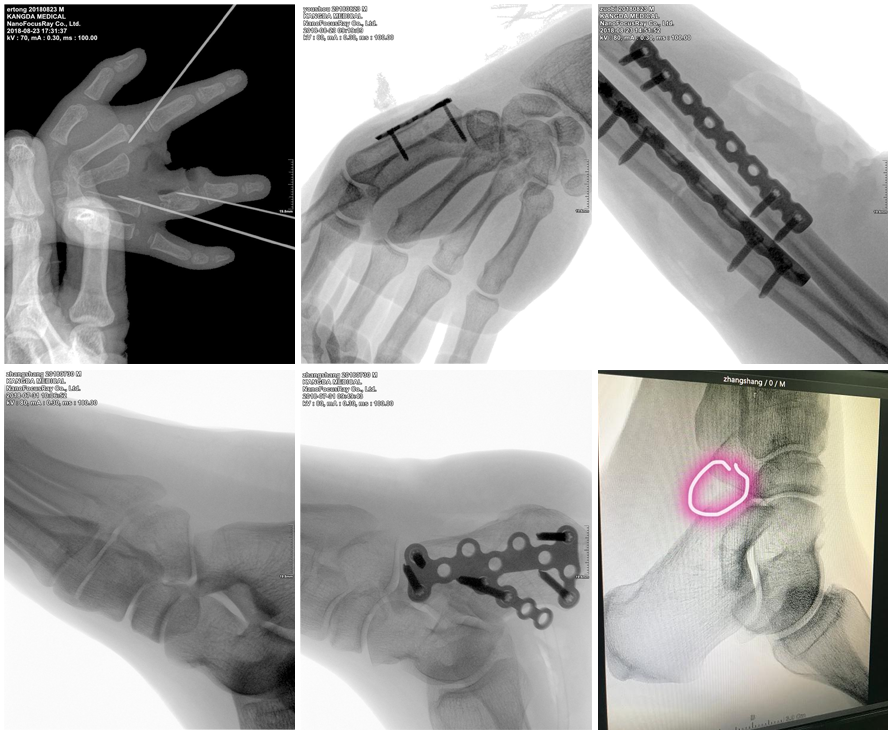

出类拔萃的高清晰数字影像链

出色的数字影像链是高清晰无损影像输出的保证。KD-CMN100 采用原装进口的微焦点球管和高分辨率平板探测器,加之优质的 X 线控制技术和强大的图像均衡技术, 为用户呈现出类拔萃的高清晰、高对比度影像图像。

原装进口微焦点球管

CMN100 全套 X 射线发生组件均为 GBT 原装进口,有效保证输出 X线的品质。 24W 输出功率,即使在较厚/较胖体位成像时也毫无压力;33μm 微米级焦点,相较普通放射 X光机的 mm 级焦点更小,使其在临床手足外科中成像更为清晰

原装进口高分辨率平板探测器

随着数字成像技术的不断成熟与发展,数字平板成像已经被广泛应用于各种放射医疗装备中,逐渐迭代影像增强器模拟成像方式。 数字化成像图像较影增成像图像而言,在成像速度、图像后处理、图像显示、图像传输、图像存储、图像分辨率和图像信息显示等各方面均有着显著优势。 由于小型平板应用成本的逐渐降低,使得数字平板探测器应用于骨科成为可能。 CMN100 采用Rayence 原装手足外科专用非晶硅/碘化铯平板探测器,49.5μm 微米级像素尺寸及 2352×2944 像素矩阵,比普通影增小 C 像素高达 7 倍、比普通平板小 C 像素高达 3-7 倍,为临床提供超精细手足外科成像

拥有高精尖技术的 CMN100,以其迷人的设计、领先的技术和非凡的性能成为便携式 mini-C 的代表产品,在手足外科临床上获得高度的评价和认可。